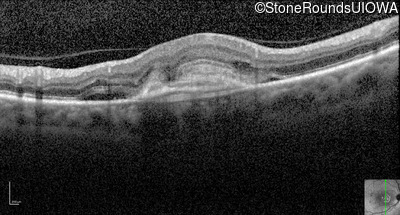

Optical Coherence Tomography - Right - 20/250

Exemplar / OCT Stack

Infrared Fundus Photograph - Right - 20/250